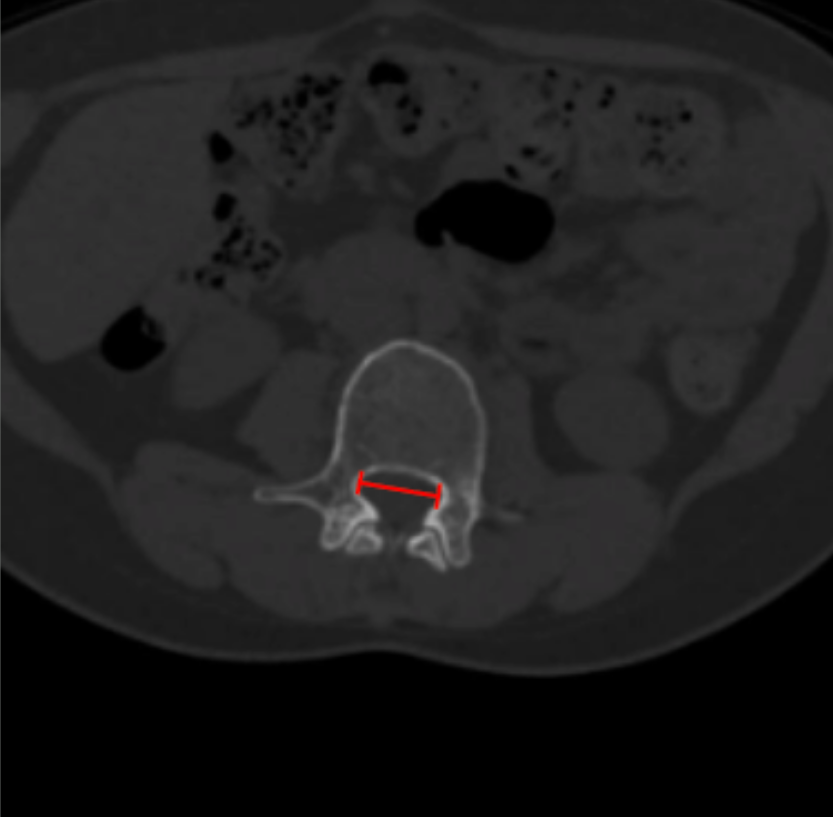

Interpedicular Distance

1) Description of Measurement

Interpedicular distance (IPD) is the transverse distance between the medial cortices of the right and left pedicles at a given vertebral level. It reflects the developmental width of the bony spinal canal and is essential for distinguishing congenital (developmental) lumbar spinal stenosis from acquired degenerative narrowing.

2) Instructions to Measure

• Identify the lumbar level to be evaluated on sagittal or coronal reconstructions.

• Scroll to the axial CT slice through the mid-pedicle level.

• Identify the medial cortical margins of the right and left pedicles.

• Draw a straight line between these two points, measuring the maximum transverse distance (mm).

• Repeat at adjacent levels to identify segmental or multilevel narrowing.